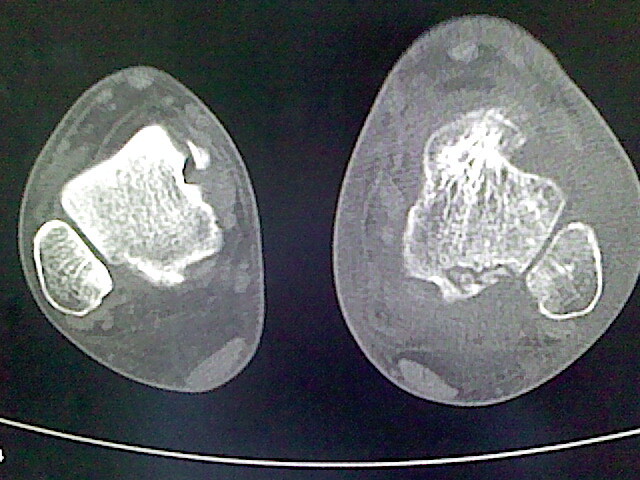

标题: CT16814:男,76岁,左小腿疼痛,不能站立 大家给看看 [打印本页]

男,76岁,左小腿疼痛,不能站立

本例骨质改变主要表现为滑膜或韧带区的骨侵蚀融解(胫腓联合区骨质破坏无硬化边),距骨后部骨质破坏区有硬化边及死骨样改变.所以,本例考虑关节结核可能性大,绒毛膜结节性滑膜炎多发于中年,且极少见于膝髋以外的关节,骨质硬坏也以压陷吸收为主,有明显的硬化边,骨膜增生呈结节状(可以mr鉴别),所以本例暂除外.

另不除外可引起相似表现的其他炎症如布氏杆菌性关节炎等